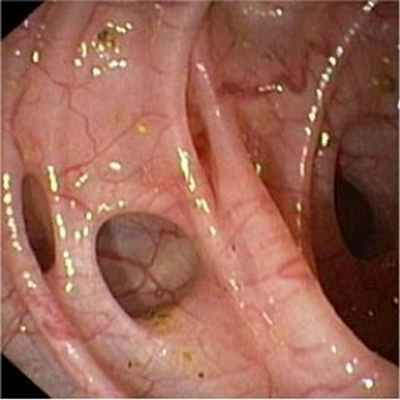

Клинические проявления дивертикулеза толстой кишки и его осложнений не могут служить основанием для установления точного диагноза заболевания. Диагностика и дифференциальная диагностика дивертикулеза толстой кишки основывается на анализе клинических проявлений заболевания и результатах обязательного рентгенологического и эндоскопического исследований толстой кишки.

![Дивертикулез лечение]()